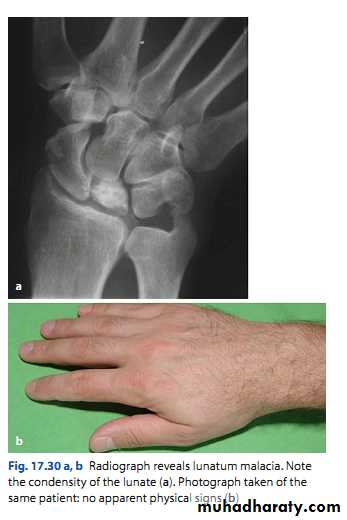

Kienbӧck’s disease

Ischemic necrosis of the lunate bone.Associated with excessive loading of the lunate.

Clinical features:

Pain and stiffness of the wrist.

Tenderness over the lunate bone.

Limitation of movement.

4 stages:• Ischemia without changes, normal x-ray, MRI changes.

• Trabecular necrosis, new bone formation, x-ray show increased density.

• Bone collapse; x-ray show small irregular lunate bone.

• Secondary OA of the wrist.

Early: splintage for 6-12 weaks.Late: surgical treatment eg, wrist arthrodesis.